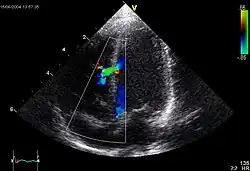

![]() |

Mitralstenose

Klinik: Leistungsminderung durch die diastolische Füllungsstörung mit Reduktion des Herzzeitvolumens (HZV), Belastungsdyspnoe, spät: Facies mitralis („rote Bäckchen“), periphere Zyanose, Zeichen der Rechtsherzinsuffizienz, Tachyarrhythmia absoluta bei Vorhofflimmern.

Kompl.: Vorhofdilatation mit Vorhofflimmern und evtl. Vorhofthrombose und Embolie, Rückstau in die Lunge (Lungenstauung, Lungenödem) und ggf. bis in den großen Kreislauf (pulmonale Hypertonie, Rechtsherzbelastung/Cor pulmonale, Rechtsherzinsuffizienz), bakterielle Endokarditis.